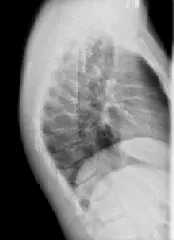

Рентген грудного відділу робитися в 2-ух проекціях (в прямій та боковій), в положенні лежачи. А, в разі викривлення, для оцінки різниці в відхиленні хребетного стовпа, робляться знімки в одній проекції, стоячи і так само лежачи – це дає можливість судити про стабільність або нестабільність хребта.

Для проведення рентгена грудного відділу хребта в бічній проекції, пацієнт лягає на бік (який саме, особливої різниці немає). Руки відводяться від досліджуваної зони, ноги (для більшої зручності) згинаються в колінах і злегка підтискаються до тулуба.